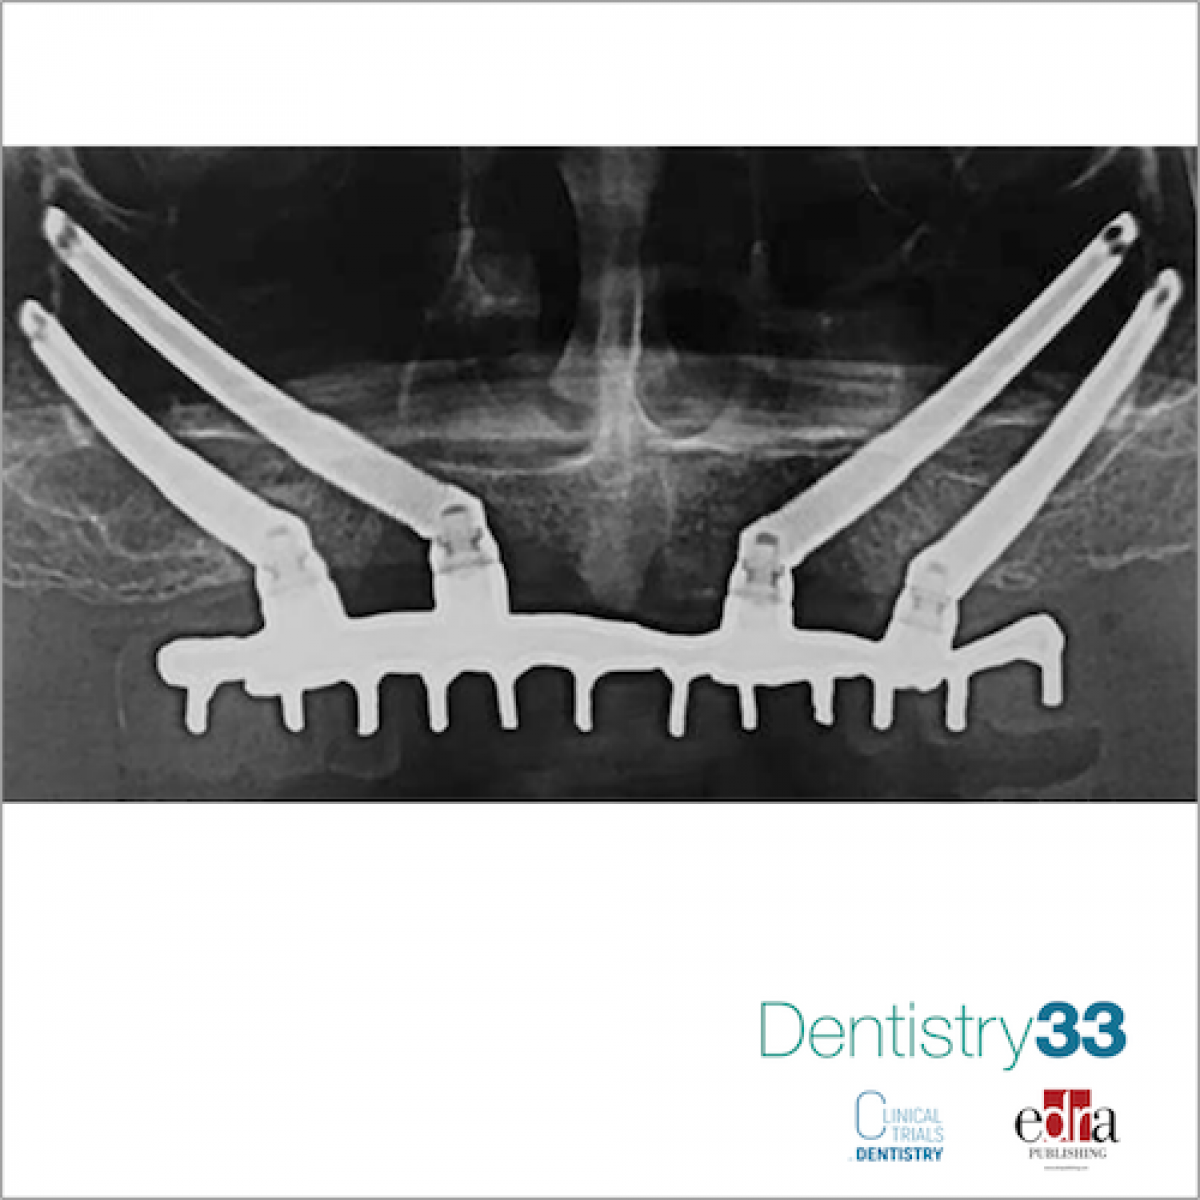

To compare the clinical outcomes of immediately loaded cross-arch maxillary prostheses supported by zygomatic implants versus conventional implants placed in augmented bone.

Seventy-one edentulous patients with severely atrophic maxillae not having sufficient bone volumes for placing dental implants, or when it was possible to place only two implants of minimal diameter 3.5 mm and length of 8 mm in the frontal area and there was less than 4 mm of bone height subantrally were randomised according to a parallel-group design to receive either zygomatic implants (35 patients) to be loaded immediately or xenograft followed, after 6 months of graft consolidation, by placement of six to eight conventional dental implants submerged for 4 months (36 patients). Outcome measures were: prosthesis, implant and augmentation failures, any complications, quality of life (OHIP-14), number of days with totally or partially impaired activity, time to function, and number of dental visits, as assessed by independent assessors. Patients were followed up to 3 years after loading.